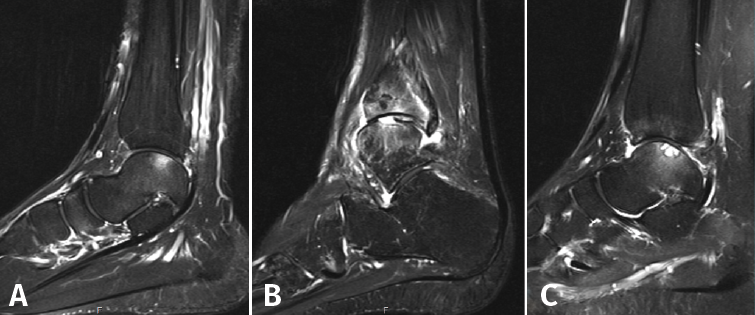

Otras clasificaciones están basadas en la tomografía axial computarizada (TAC) o en la resonancia magnética (RM) y engloban las LOC tanto agudas como crónicas. El estudio mediante TAC permite más precisión para definir el tamaño y la localización de las lesiones, así como de la presencia de cambios quísticos. Ferkel y Sgaglione desarrollaron un sistema de clasificación basado en la TAC (Figura 2), que tiene la particularidad de servir de apoyo para la planificación preoperatoria y la elección del tipo de tratamiento más adecuado (tornillo/pin, microfractura o injerto)(18).

Figura 2. Imágenes de resonancia magnética que muestran diferentes fases de lesión osteocondral. A: estadio IIA, que muestra edema óseo circundante; B: fractura osteocondral en estadio IV con un fragmento desprendido y desplazado; C: estadio V que muestra la formación de quistes subcondrales.

Hepple desarrolló un sistema de clasificación basado en la RM y que también tiene implicaciones de indicación (Tabla 2). Actualmente, la RM constituye el mejor método para evaluar la estabilidad de un fragmento mínimamente o no desplazado, lo que puede influir en la necesidad, o no, de practicar su fijación (Figura 3)(19,20).

Tanto la TAC como la RM son más sensibles y han demostrado una precisión similar cuando se emplea la TAC helicoidal de alta resolución(25). La RM puede delinear mejor el cartílago y distinguir entre cartílago nativo y reparativo (fibrocartílago); también puede valorar mejor los cambios del tejido sinovial(26). Además, la secuencia de mapeo T2 de RM puede proporcionar información suplementaria sobre la matriz del tejido reparador(27,28). Otra de las ventajas de la RM frete a la TAC la constituye la visualización de la patología concomitante de los tejidos blandos. Sin embargo, presenta una desventaja al evaluar el edema óseo circundante, lo que tiende a sobrestimar el tamaño de la lesión, especialmente porque el tamaño de la lesión dicta el tipo de tratamiento y el pronóstico, haciendo necesario evaluar con precisión el tamaño cuando se propone el tratamiento(29,30).